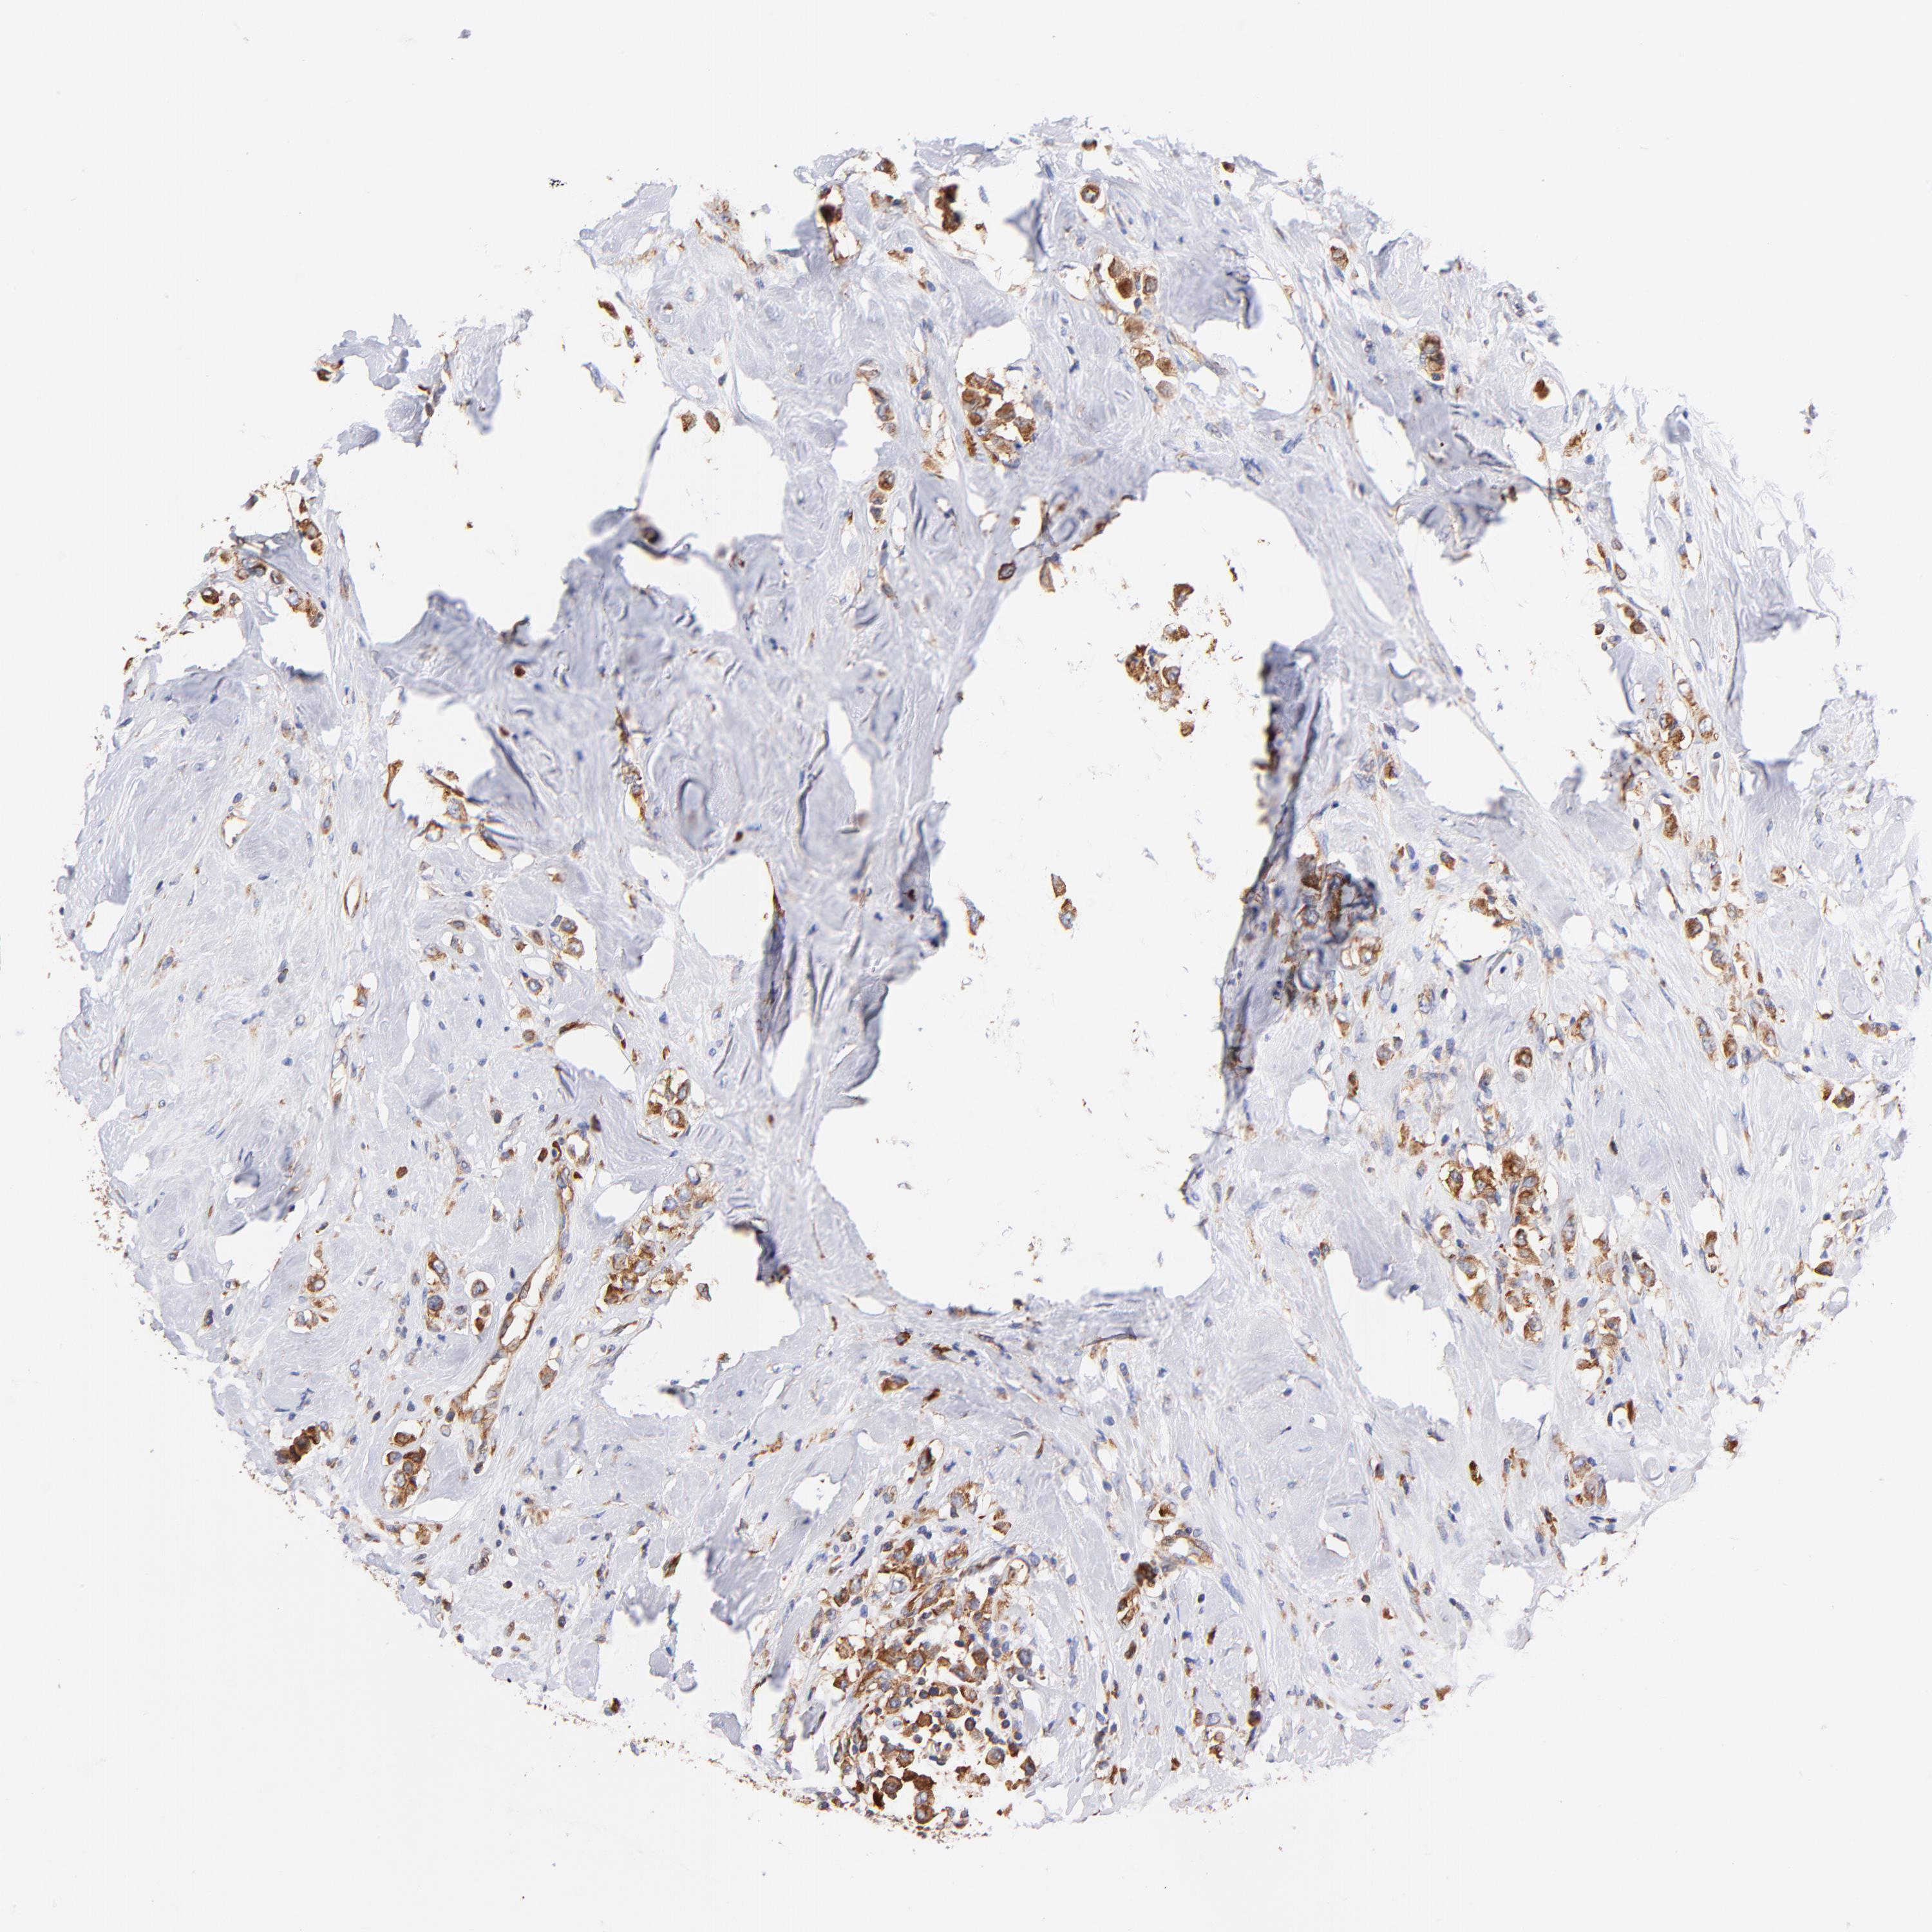

CANCER BREAST CANCER Show tissue menu

BRCA TCGA BRCA VALIDATION PROTEIN EXPRESSION